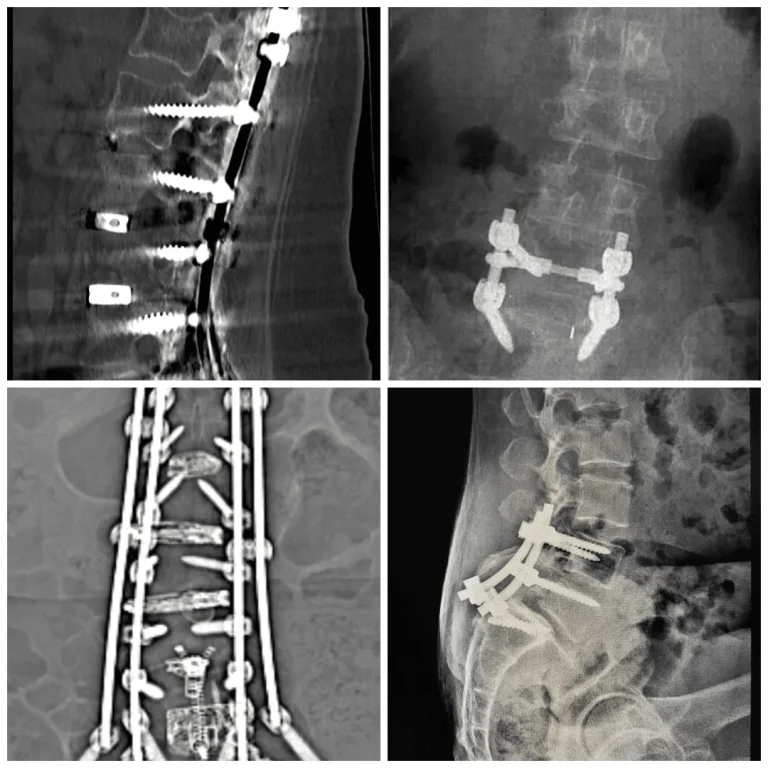

Spinal Fusion Surgery X-ray images showing spinal fusion with screws and rods.

Step 6: Drill & Bolt Screws, Rods & Plates

Holes are drilled into the vertebrae to bolt pedicle screws, connecting rods, or metal plates onto the spine.

CT scan showing spinal instrumentation with screws and rods in place.

X-rays of spinal surgeries showing metal screws and rods in the spine.

90%+ Need Additional Surgery